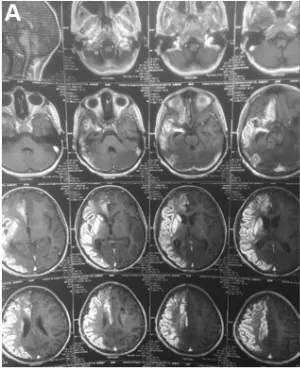

脑血管数字减影血管造影(DSA)检查显示:双侧颈内动脉完全闭塞(右侧位于眼动脉远端,左侧位于后交通动脉远端),基底节区形成烟雾状侧支循环血管。脑部MRI检查证实右侧大脑中动脉及大脑前动脉供血区存在急性缺血性改变。

术前DSA影像清晰显示双侧颈内动脉、右侧眼动脉远端和后交通动脉远端完全闭塞,双侧基底节区可见典型烟雾状血管网络形成。